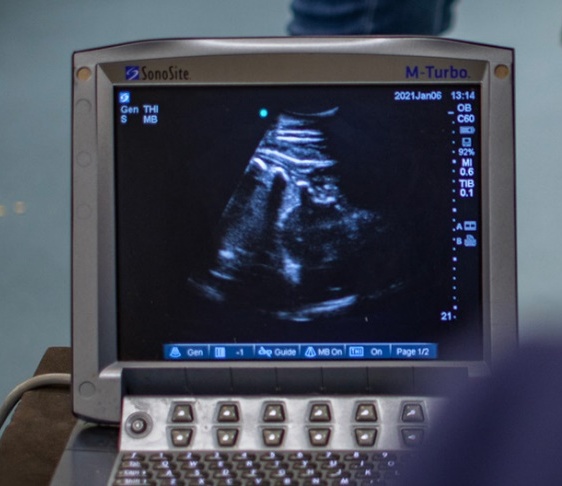

Pre-breeding checks are routine ultrasound scans of the uterus, ovaries, and other examinations to determine the optimal time to breed. This evaluation normally includes ultrasound scans, vaginal evaluation, and all the follow-ups in order to ensure the most accuracy of breeding. Each mare is treated to suit her needs and/or difficulties according to each animal's individuality.

The recipient mare will be checked between 12 to 14 days (embryo age) to determine confirmation. Follow-up will be done at 30 days of pregnancy to ensure the embryo has a heartbeat and viability confirmation. Follow-ups on these mares are necessary every couple of weeks until 2 months, which is the critical period.

• Ultrasound examination